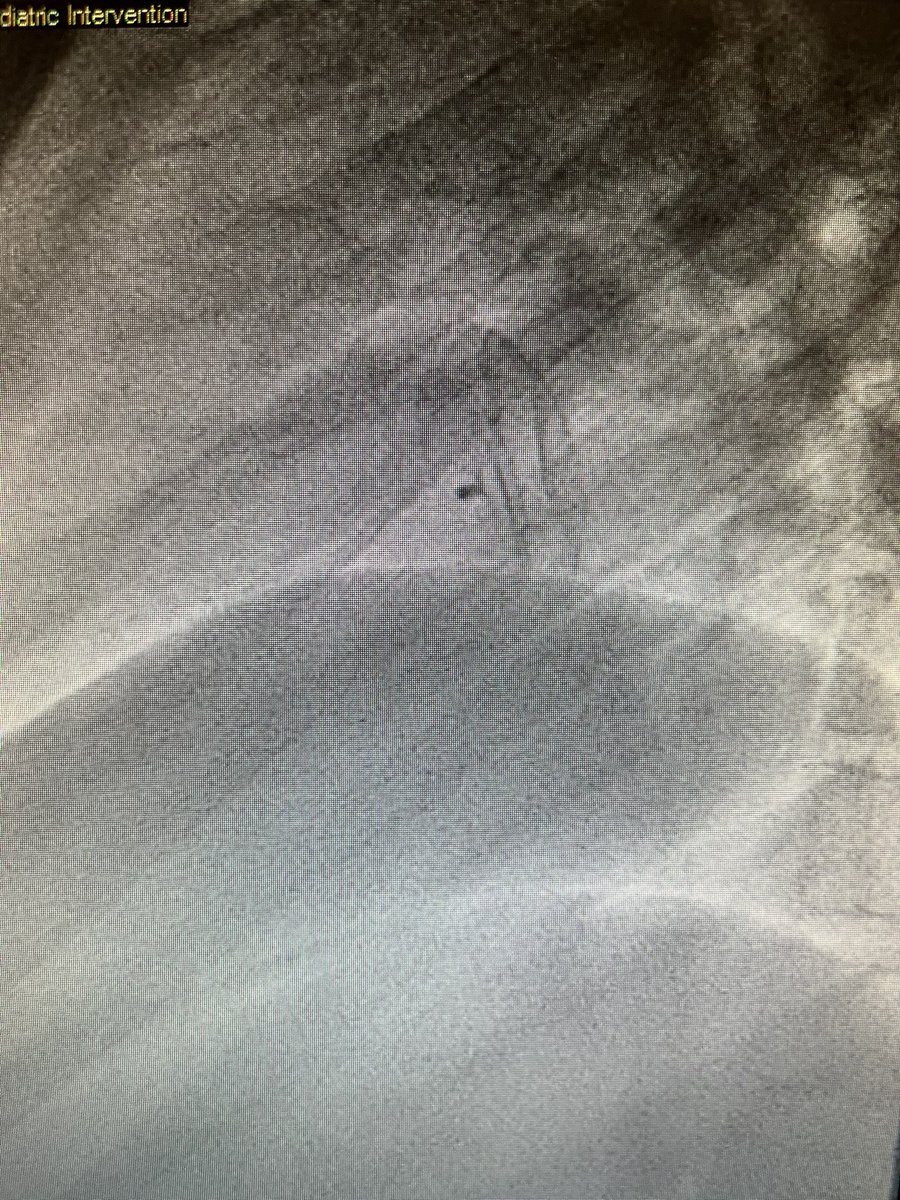

#Fontan patients offer unique challenges! Teenager with #HLHS post Fontan with recoarctation and LPA stenosis. LCA ran along the course of the LPA. Did coronary compression testing but able to stent both with good result. #CHD #ACHD @NCProvider @Adam_Skaff @SohamDasguptaMD 1/2